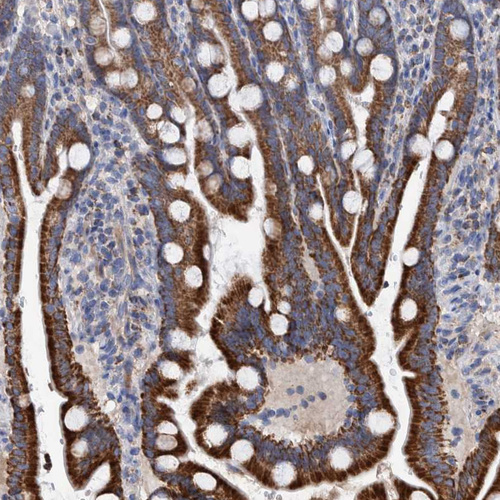

Immunohistochemistry analysis in human liver and placenta tissues using HPA023160 antibody. Corresponding DECR1 RNA-seq data are presented for the same tissues.